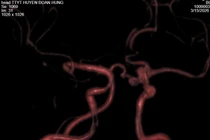

phinh-mach-3.jpg

Hình ảnh DSA mạch não sau can thiệp nội mạch xử trí túi phình bằng coil có hỗ trợ stent - Ảnh BVCC